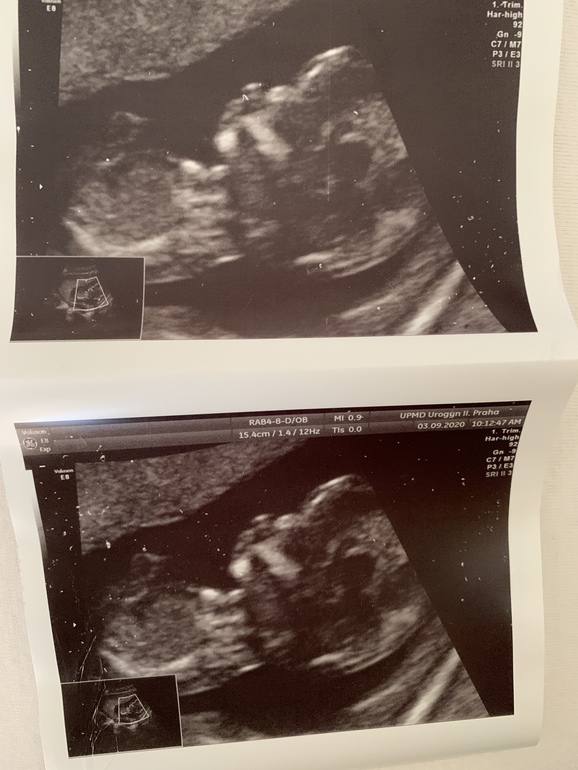

Прошла сегодня наш долгожданный скрининг , срок поставили 13+2, хотя по 2 узим должно было быть 12+5.

Все у нас хорошо растём , сердечко 157 ударов

Дата родов на 9 марта 2021🙏🏻💙

Пол не сказали, зажал ноги и не показался. Надеюсь все таки на мальчишку 🙏🏻🙏🏻.